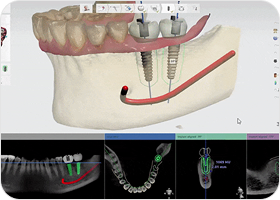

세심한 사전 진단 및 식립 계획

치료 전 3D 디지털 진단을 통한

수술 계획으로 예기치 않은

부작용을 줄일 수 있습니다.

3D 디지털 가이드로 정확하고

빠른 진료가 가능합니다.

저선량 3D CT

저선량 3D CT를 통한 환자의 잇몸뼈 상태,

신경위치를 데이터화하여 정밀한 계획을 수립합니다.

3D 구강스캐너

3D 구강스캐너로 치아와 잇몸 형태를 동일하게

스캔하여 최적의 임플란트 식립 각도와 위치를 검토합니다.

디지털 수술 가이드

잇몸을 절개하는 기존의 방식과 달리,

임플란트 식립 위치에 2mm 정도의 작은 구멍을 뚫어 식립을 진행하여

잇몸 손상과 통증은 줄이고, 빠른 회복이 가능합니다.